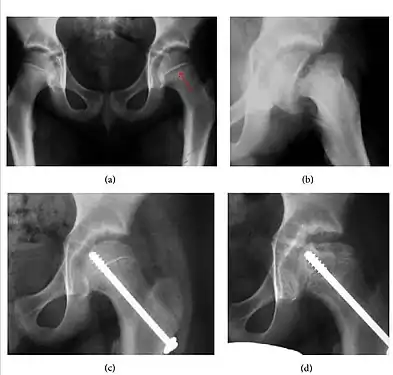

Slipped capital femoral epiphyses (SCFE) usually affect 11- to 14-year-old adolescents (Figure 4). Radiographs may show widening and irregularity of the physis and posterior inferior displacement of the capital femoral epiphysis. On the AP view Klein’s line, tangent to the lateral aspect of the femoral neck, does not intersect the femoral head indicating that it is displaced. SCFE may compromise the blood supply to the femoral head and cause avascular necrosis, mainly when there is instability between the fragments.[1]

Figure 4: (a) X-ray of a 10-year-old child with left hip pain. It was considered normal at emergency despite the widening of the left physis (arrow). Two weeks later epiphysiolysis was evident (b). Despite appropriate surgical reduction (c) osteonecrosis developed and femoral head collapsed 1 month later (d).[1]

Figure 4: (a) X-ray of a 10-year-old child with left hip pain. It was considered normal at emergency despite the widening of the left physis (arrow). Two weeks later epiphysiolysis was evident (b). Despite appropriate surgical reduction (c) osteonecrosis developed and femoral head collapsed 1 month later (d).[1]